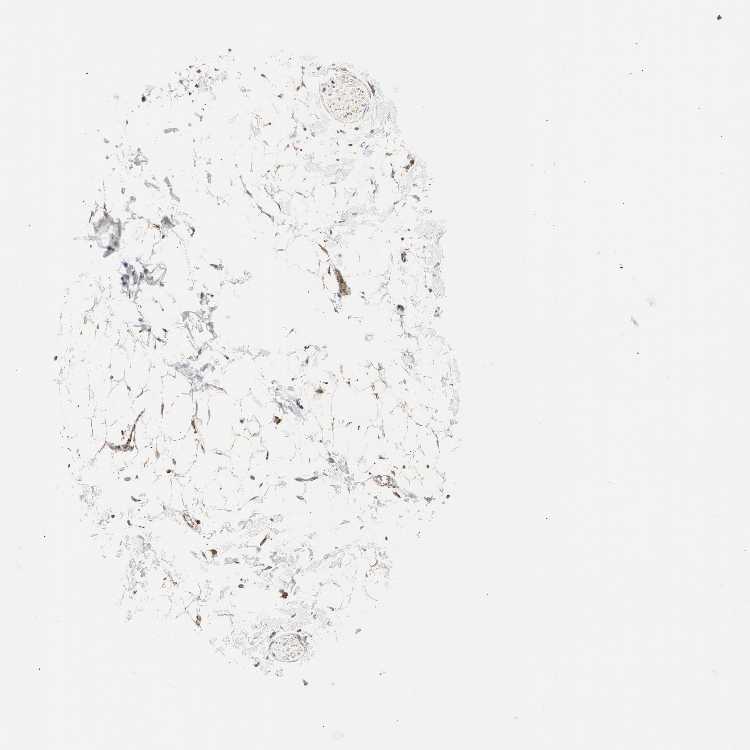

ADIPOSE TISSUE - Antibody stainingi

Antibody staining in the annotated cell types in the current human tissue is reported as not detected, low, medium, or high, based on conventional immunohistochemistry profiling in selected tissues. This score is based on the combination of the staining intensity and fraction of stained cells.

Each image is clickable and will lead to virtual microscopy that enables deeper exploration of all samples and also displays staining intensity scores, fraction scores and subcellular localization as well as patient and tissue information for each sample.

Antibody HPA003037

Adipocytes Medium